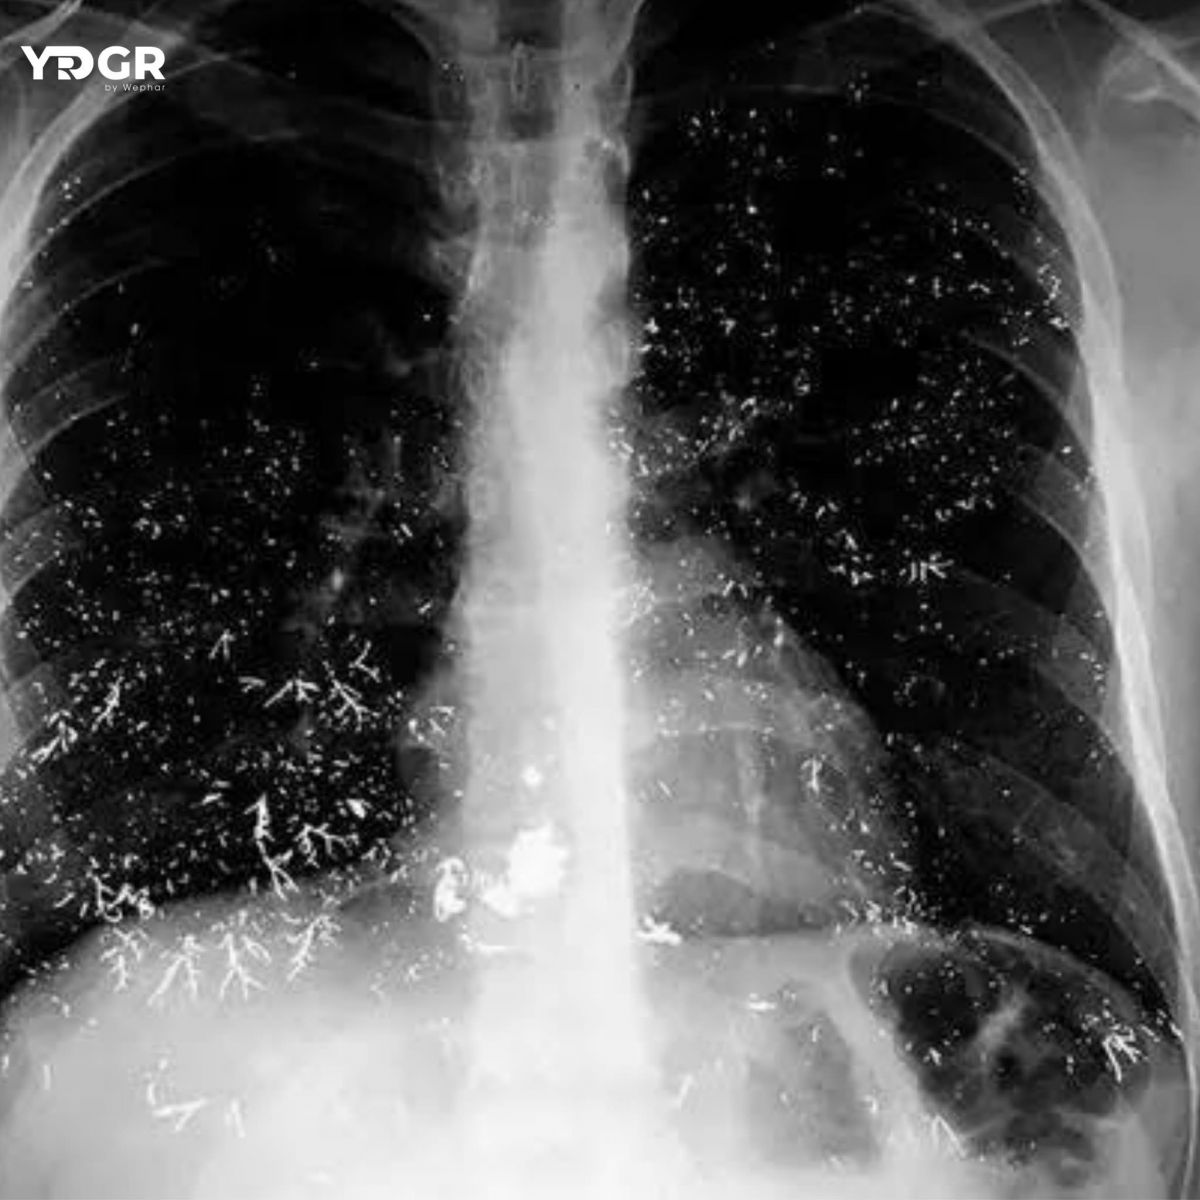

🩻 Hình ảnh X-quang ngực bên dưới cho thấy nhiều đốm cản quang dạng kim loại ở cả hai đáy phổi, một phần nằm dọc theo cây phế quản.

CT ngực xác nhận các tổn thương tương ứng. Nồng độ thủy ngân trong nước tiểu đo được 172 μg/g (cao hơn giới hạn bình thường 11,5–36,5 μg/g).